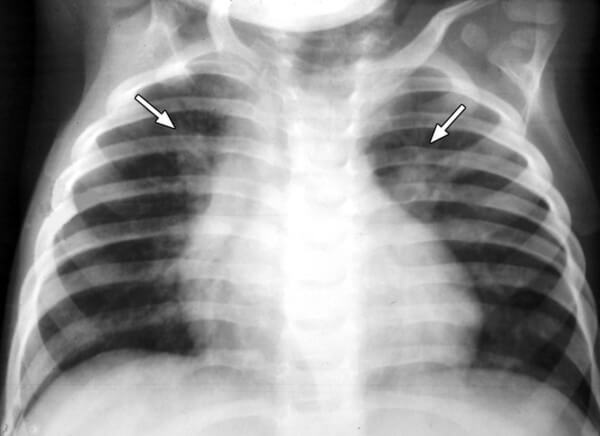

Диагностика пневмонии у детей с помощью рентгена вызывает ряд некоторых трудностей. Связано это с небольшим объемом легочной ткани и большим количеством структурных элементов на маленькую площадь, которая подлежит исследованию. Из-за этого появляется сложность в правильной оценке легочного рисунка, а также диагностирования состояния легочных корней и лимфоузлов.

Самым распространенным признаком пневмонии у детей, которые проявляются на снимках, являются очаговые тени в нижних сегментах легких диаметром 1-2 мм.

На снимке видны отдельные небольшие очаги поражения ( 1-1,5 см), расположенные в одном из легких (при билатеральной форме – в обоих). Заметным в данном случае будет расширение корней легких из-за наполнения жидким экссудатом.

- Очаговая форма. На рентгене отображаются небольшие (1-1,5 см) тени со слабой или умеренной интенсивностью окраски, неоднородной структурой и нечеткими границами. Очаги поражения могут быть единичными или множественными, а в некоторых случаях они сливаются в одно большое пятно. Корни легких расширены, причем нарушения нормального рисунка органа могут сохраняться в течение нескольких дней после выздоровления.